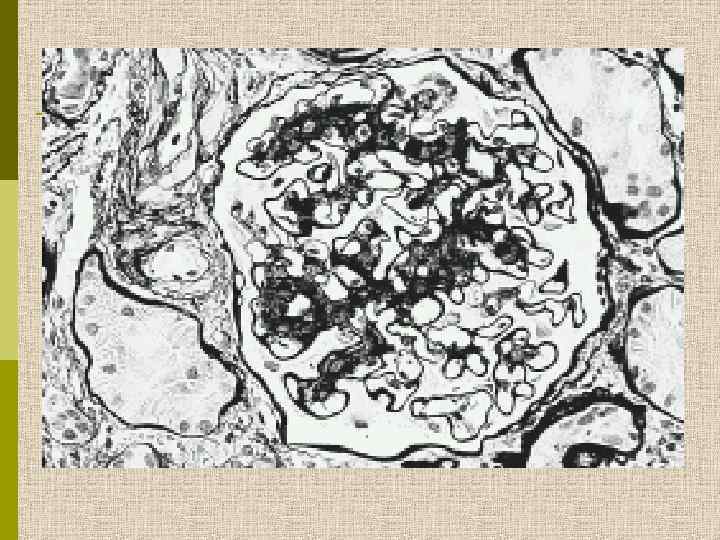

МОРФОЛОГИЧЕСКИЕ ИЗМЕНЕНИЯ ПРИ ДИАБЕТИЧЕСКОЙ НЕФРОПАТИИ Основные варианты - диабетический гломерулосклероз с узелками Kimmelstiel-Wilson - диффузный мезангиальный гломерулосклероз Характерные признаки Утолщение ГБМ; артериолярный гиалиноз; аневризматические капилляры; капсулярные капли; фибриновые шапочки; атрофия канальцев; инфильтрация, расширение и склероз интерстиция; линейные отложения иммуноглобулинов

Диабетическая микроангиопатия/утолщение базальной мембраны 1. Образование аневризм 2. Утолщение базальной мембраны 3. Leakyсосуды и базальные мембраны